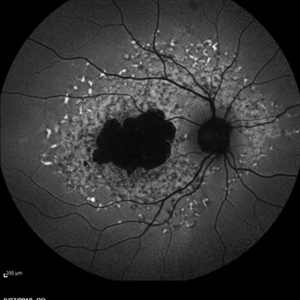

Late Stage Stargardt's Disease

Late Stage Stargardt's Disease

Mar 13 2013 by Hamid Ahmadieh, MD

Autofluorescence imaging of the left eye of a 46-year-old man with decreased VA due to advanced Stargardt's disease.

Photographer: Nayereh Hadipoor, Negah Eye Center, Tehran

Imaging device: Heidelberg Spectralis

Condition/keywords: autofluorescence imaging, Stargardt disease